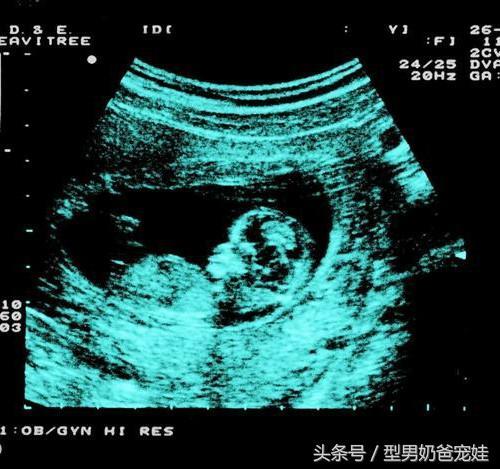

★第23周,是进行大排畸检查的良好阶段,可以做四维了哦。如果四维的结果中有肾盂分离的字样是男孩的面大,而肾盂未见明显分离是女孩的面大哦!